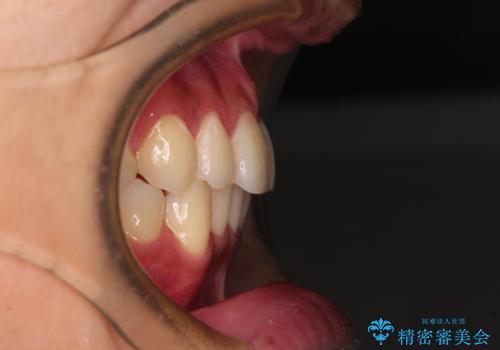

- 矯正治療の後戻りを気にして来院された患者様です。

後戻りは軽微であったので、インビザライン・ライトにより矯正治療を行うこととしました。

矯正治療後は、再度後戻りすることを極力回避するために、下顎前歯の舌側を細いワイヤーを用いて保定することとしました。